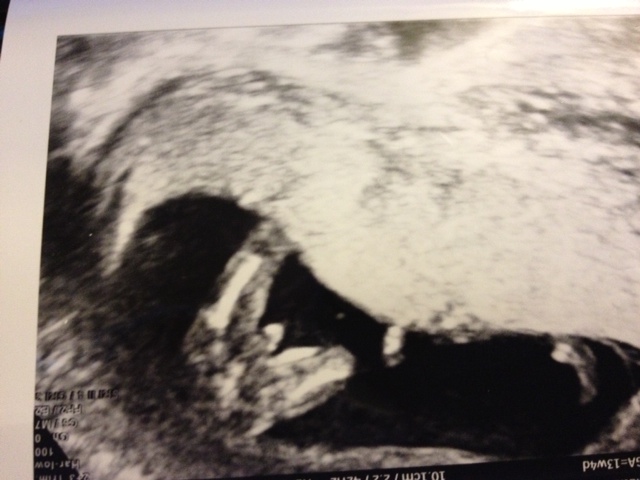

Hi, all! New here and probably asking a silly question. I was around 13 weeks 2 days to 13 weeks 4 days when these potty shots (all doc looked at) made the doc say definitely a boy. I *think* there is also a nub shot, so I'll post it too. Definitely a boy?

potty shot 2

nub shot??